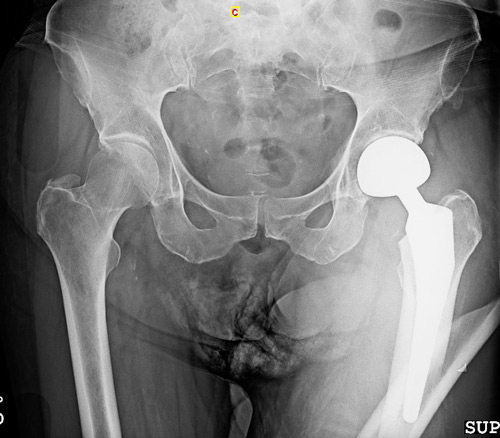

This clinical case presents the management of a periprosthetic femoral fracture occurring shortly after hemiarthroplasty in a 68-year-old patient. Based on the initial clinical presentation and imaging findings, how would you approach fracture assessment in this situation?

• 68 year-old female

• Walks with a walker because of a hydrocephaly treated 20 years ago

• Left bipolar hemiarthrosplasty implanted 2 weeks ago for a Garden 4 neck fracture

• Fall while walking

Imagery